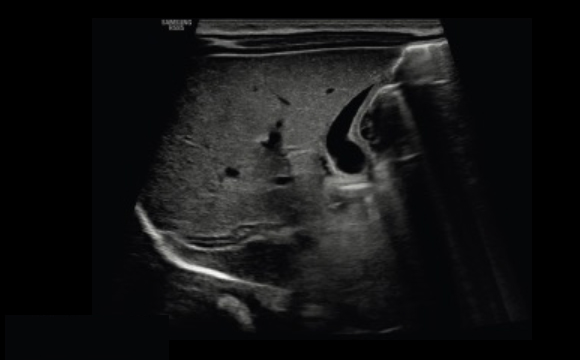

Addome a

Attenuazione delle aree sfocate nelle immagini

HQ-Vision™ ¹ fornisce immagini più chiare mitigando le aree dell'immagine che risultano più sfocate rispetto alla loro effettiva natura